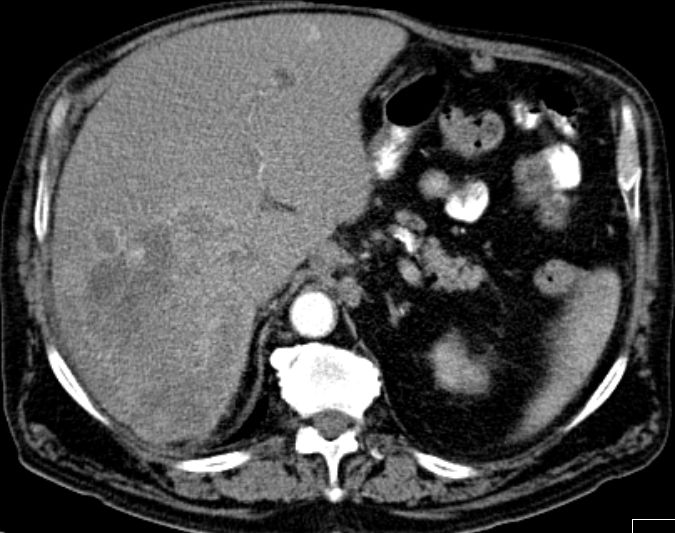

| CT | 61-jähriger trockener Alkoholiker mit bekannter Leberzirrhose und Ascites.

Mehrere Raumforderungen in der Leber. AFP 84. Keine Tumorzellen im Ascites.![]() | ||